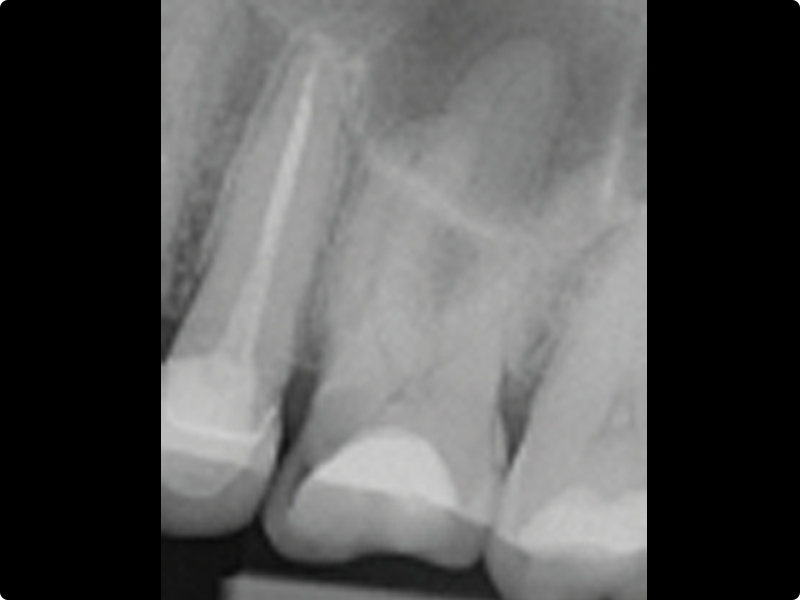

• Endodontic retreatment: why, when, and how to retreat

• Redefining a proper access cavity

• Removal of intracanal retainers: metal posts, fiber posts, zirconia posts

• Removal of root canal filling materials